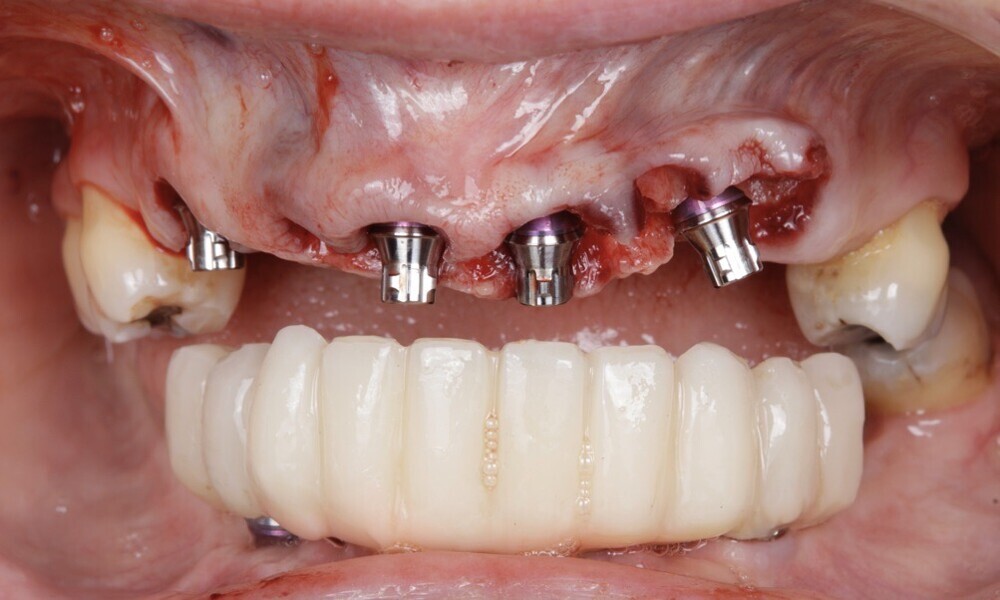

After treating the mandibular arch, we proceeded with the maxillary arch. The flap design involved a flapless approach for the maxillary arch. All teeth in the maxillary arch were extracted, except for the molars (Figs. 51 & 52). The provisional restoration was seated and adapted to the mouth after the tooth extractions (Figs. 53–55). The implant sites were prepared following the manufacturer’s instructions, the implants were subsequently inserted and screw-retained abutments (Straumann) were placed (Figs. 56 & 57). Guided bone regeneration with Straumann XenoGraft and a resorbable membrane (Straumann) were then performed (Figs. 58–60).

Figs. 56–60: The implants were placed, guided bone regeneration was performed using a xenograft and screw-retained abutments were placed.

The soft tissue was in good condition, and the definitive restorations were placed (Figs. 76 & 77). After placing the definitive restorations, oral hygiene instructions were given to ensure proper care and prevent complications. Additionally, the occlusion was carefully checked and adjusted as needed (Figs. 78–83).

Figs. 76 & 77: Optimal soft tissue conditions were observed, indicating readiness for the definitive restorations.